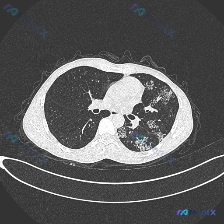

双肺多发实变磨玻璃影,这个胸部CT大家第一步怎么考虑?

整理了一份胸部CT影像分析资料,和大家一起讨论这个病例。 影像核心异常:双肺弥漫性病变,左肺上叶可见大片融合实变影,密度较高边界模糊,其内可见支气管充气征,实变周围伴磨玻璃密度影及条索影;右肺可见多发散在斑片状、结节状磨玻璃影及实变影;双肺部分区域可见小叶间隔增厚和细微网格影。 整体是多形性病变,同...